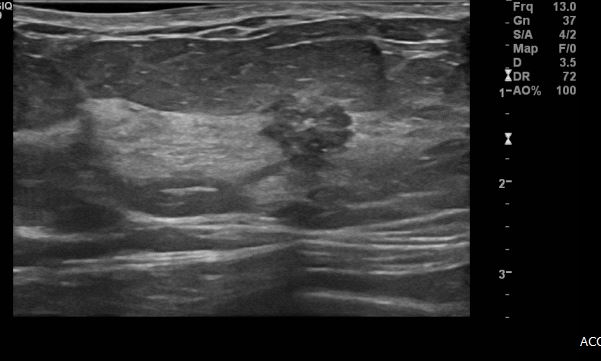

상기환자 건강검진상 이상 소견으로 내원하신 60대 여성분으로  좌측 상외사분면의 의심스로운 혹 조직검사 시행하여 좌측 침윤성 유관암 진단 되었습니다.